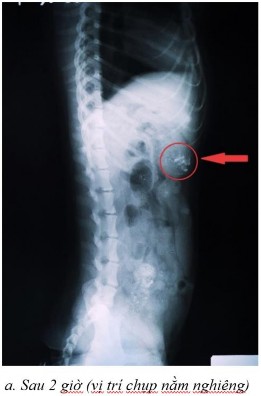

Một số dữ liệu đánh giá sự dịch chuyển in vivo trong đường tiêu hóa chó bằng phương pháp hình ảnh x-quang

Phụ lục 5.1. Hình ảnh X-quang chó 2 ở thời điểm (a) sau 2 giờ ở vị trí nằm nghiêng, (b) sau 4 giờ ở vị trí nằm ngửa, (c) sau 4 giờ ở vị trí nằm nghiêng, (d) sau 7 giờ ở vị trí nằm ngửa, (e) sau 7 giờ ở vị trí nằm nghiêng, (f) sau 9 giờ ở vị trí nằm ngửa, (g) sau 9 giờ ở vị trí nằm nghiêng, (h) sau 11 giờ ở vị trí nằm ngửa và (i) sau 11 giờ ở vị trí nằm nghiêng